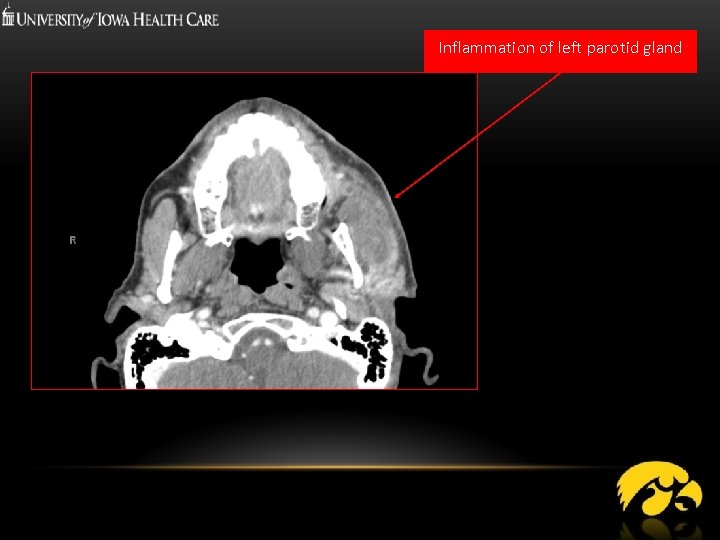

Inflammation of left parotid gland

INDICATIONS: Optimal: - Inflammatory pathologies, infection Obstructive pathologies: stones Occasional: - CT sialography, ductal pathology Masses Post radiation

ADVANTAGES - Quick - Readily available - Gross anatomical detail of surrounding structuresextent of inflammation - High sensitivity for Stones/calcifications - 3 D reconstructions: CT Sialography